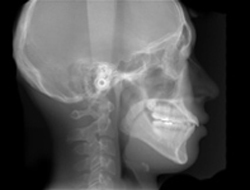

矯正治療では正確な診断と適切な治療計画を立てることが最も重要です。そのためには歯の模型、レントゲン写真、歯や顔そして姿勢の写真などの基本検査が必要となります。